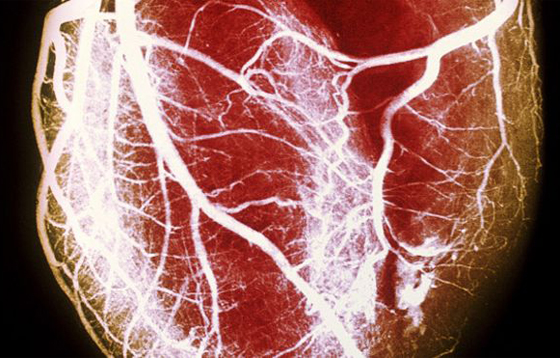

الصورة للتوضيح فقط

وتحدث الإصابة عندما تضيق الشرايين التي تغذي القلب بالدم بسبب ترسبات دهنية على جدارها، وإذا حدث تجلط في الدم فقد يؤدي إلى انسداد الشرايين فتحدث الإصابة بالنوبة القلبية.وقال البروفيسور ساماني " باستخدام البحث الجيني على نطاق واسع، أصبحت هذه أول دراسة تثبت أن العلاقة بين طول القامة وانخفاض نسبة خطر الإصابة بأمراض القلب تعود إلى عوامل جينية وليست عوامل خارجية بسبب الأنشطة الحياتية".